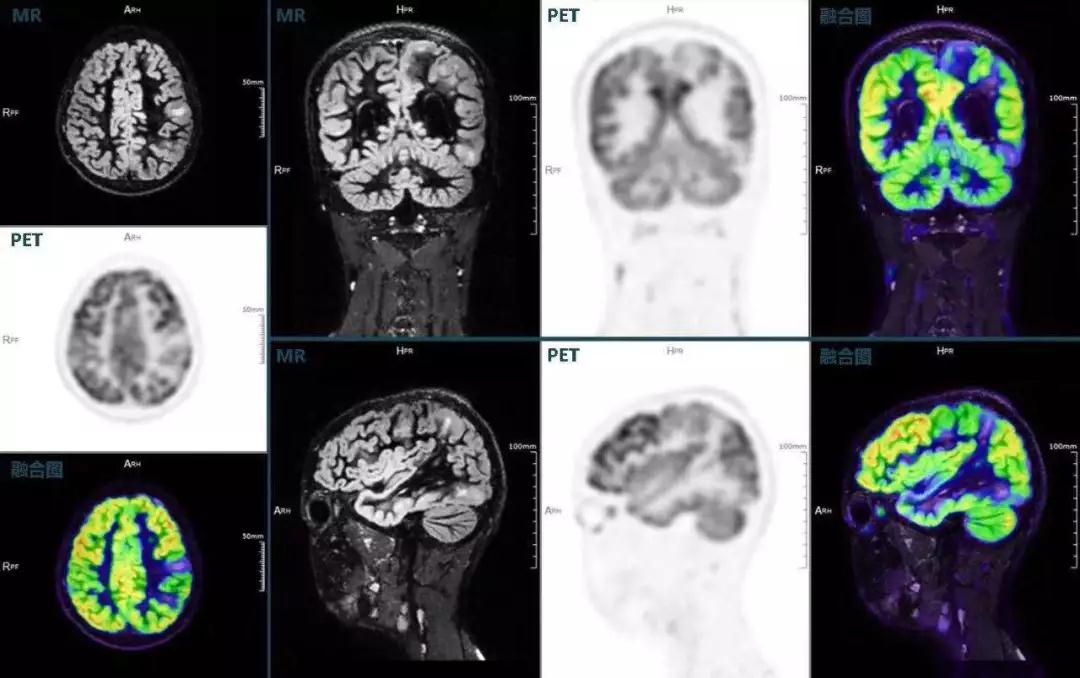

不僅如此,聯(lián)影“時空一體”超清TOF PET/MR還搭載了大量可用于神經(jīng)疾病領(lǐng)域的高級應(yīng)用,如DIR(Double Inversion Recovery雙反轉(zhuǎn)恢復(fù))序列能夠清晰顯示大腦皮層的結(jié)構(gòu)成像,對于皮層腫脹,膠質(zhì)增生等癲癇的影像征象都能清楚呈現(xiàn);DTI(Diffusion Tensor Imaging彌散張量成像)高級應(yīng)用能夠顯示細(xì)小的神經(jīng)纖維束缺損,以更加定量的形式為醫(yī)生提供一個全新的診斷維度,輔助醫(yī)生精準(zhǔn)診斷。

(結(jié)節(jié)性硬化,MR DIR序列清晰顯示腦皮層病理改變,PET顯示了病灶區(qū)域FDG的低濃聚。PET/MR融合顯像同時提供了結(jié)構(gòu)異常改變和功能變化的信息。)